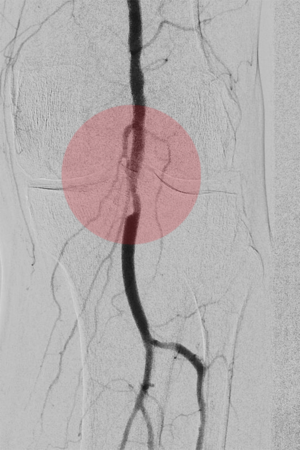

2. Angioplastie/ PTA – Gefäßweitung

Einengungen oder Verschlüsse von Gefäßen können durch Ballonkatheter beseitigt werden. Dazu werden die Ablagerungen in den Gefäßen zerteilt und in die Gefäßwand gedrückt, um so diese Stelle wieder zu glätten.

Neben sogenannten Normalballons kommen auch spezielle andere Arten von Ballonkathetern zur Anwendung. Dazu gehören u. a. Schneidballons oder Ballons die Stoßwellen abgeben, für sehr harte Gefäßablagerungen. Auch Ballonkatheter mit einer medikamentösen Beschichtung, die an die Gefäßwand abgegeben wird, um den arteriosklerotischen Gefäßumbau zu bremsen, werden eingesetzt.